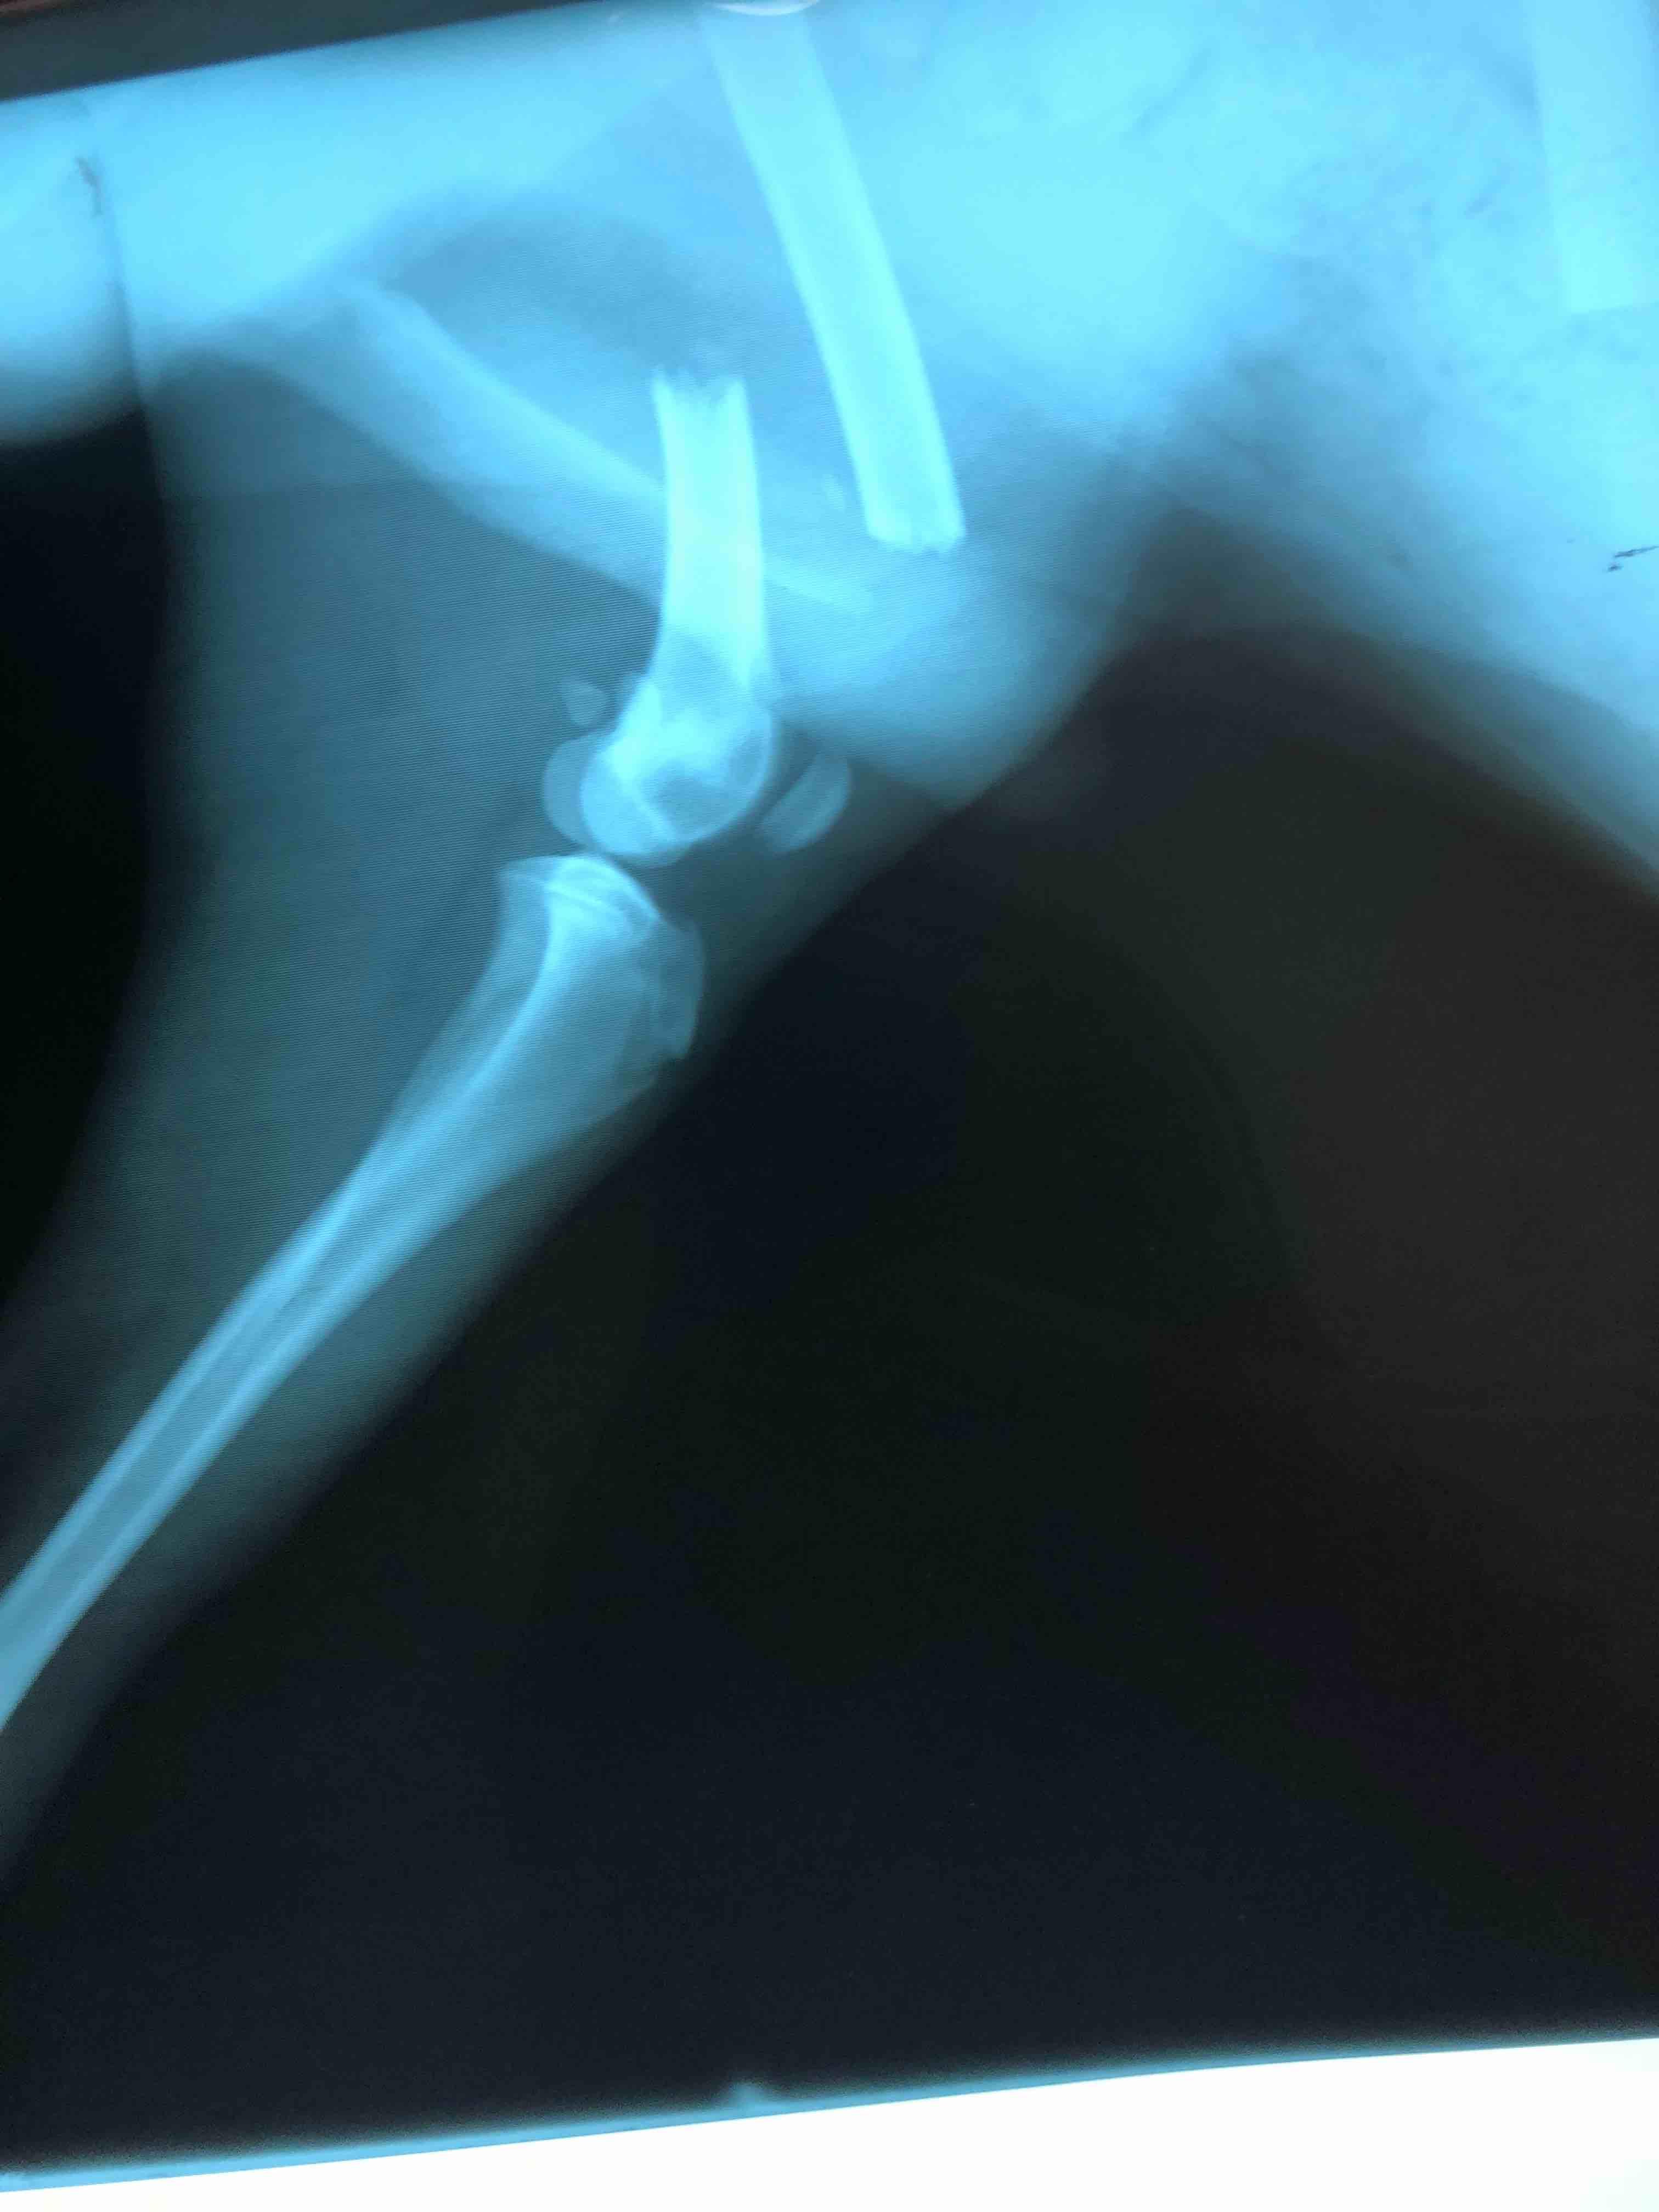

My dog was ran over by a car about a year ago and he had surgery on his leg. The put a rod on the inside of his leg to help the bone grow back together but they never took it out and I’m afraid that he might get an infection or something. The rod has been in there for a while. What do I need to do? I attached pictures of the X-Ray and a picture of my dog. He’s bigger now.

Thanks for using Petco Pet Education Center, formerly Petcoach! In general, pins and plates can safely be left in the body indefinitely. There is always a small risk of infection, in which case the pin/plate would be removed. The risk of infection will be present life-long but is less than 5%. If you are worried about it, head into the vet for an x-ray and to discuss if it is worth taking out. (A pin that exits near the surface of the skin can sometimes be removed quickly under sedation.) Best of luck to you and Rocky!